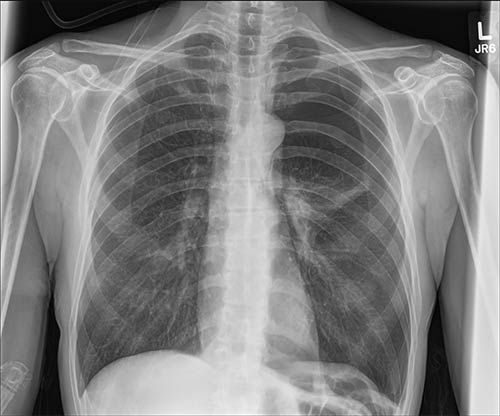

通过气胸可视化处理节省时间。它从原始曝光中生成一个相配影像,经过优化以突出呈现胸腔中的游离空气,提高诊断准确性并增强患者护理。